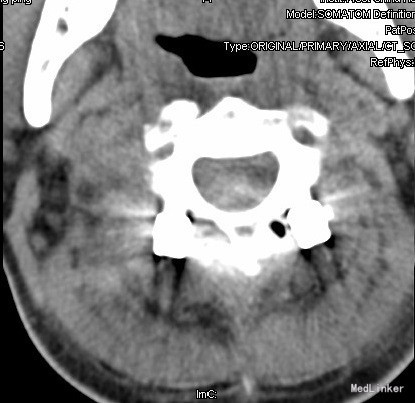

查体:查体:T:36.7oC,P:80次/分,R:20次/分,BP:137/82mmHg。神志清楚,无病容,皮肤巩膜无黄染,全身浅表淋巴结未见肿大。。颈静脉正常。心界正常,心律齐,各瓣膜区未闻及杂音。胸廓未见异常,双肺叩诊呈清音,双肺呼吸音清,未闻及干湿啰音及胸膜摩擦音。腹部外形正常,全腹柔软,无压痛及反跳痛,腹部未触及包块,肝脏肋下未触及,脾脏肋下未触及,双肾未触及。双下肢无水肿。视:平车推入病房,颈椎颈托围领固定,颈部、前额部及全身皮肤未见皮损及异常。触:颈1-4棘突及椎旁明显压痛、叩击痛,感觉正常,四肢肌张力正常。动量:颈椎活动受限,尤以旋转受限为重。双侧肱二头肌反射、肱三头肌反射、膝反射正常,双侧babinski征阴性,右侧Hoffmann征阳性、左侧阴性。 辅助检查:颈椎X线片、MRI、CT提示:寰椎椎板前弓骨折,寰枢关节旋转半脱位

诊断:1.陈旧性寰枢关节旋转脱位2.陈旧性寰椎前弓骨折 治疗:全麻下行:行经前路寰枢椎脱位切开撬拨复位+经后路寰枢椎侧块螺钉内固定、去髂骨后外侧植骨融合术